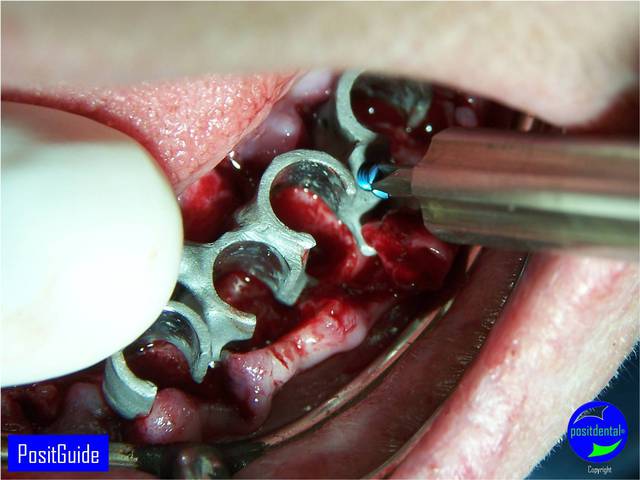

Mise en Charge Immédiate Post Extractionnelle , MCIPE partie chirurgicale de A à Z

implants in situ et S.I.A.O pré-opératoire